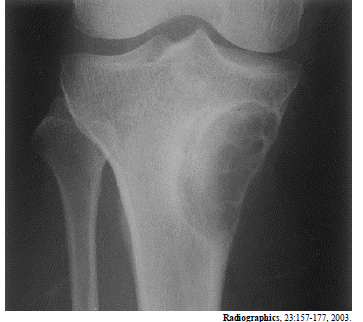

A radiografia acima é de um paciente do sexo masculino, com 25 anos de idade, com queixa de dores no joelho. Considerando essa imagem, é correto afirmar que

fibroma não ossificante é um diagnóstico diferencial adequado.

Provas

A radiografia acima é de um paciente do sexo masculino, com 25 anos de idade, com queixa de dores no joelho. Considerando essa imagem, é correto afirmar que

a lesão é do tipo metafisária.

A radiografia acima é de um paciente do sexo masculino, com 25 anos de idade, com queixa de dores no joelho. Considerando essa imagem, é correto afirmar que

a lesão tem aspecto de benignidade.

A radiografia acima é de um paciente do sexo masculino, com 25 anos de idade, com queixa de dores no joelho. Considerando essa imagem, é correto afirmar que

a lesão é predominantemente blástica.

A radiografia acima é de um paciente do sexo masculino, com 25 anos de idade, com queixa de dores no joelho. Considerando essa imagem, é correto afirmar que

o diagnóstico mais provável é de tumor de células gigantes.

A radiografia acima é de um paciente do sexo masculino, com 25 anos de idade, com queixa de dores no joelho. Considerando essa imagem, é correto afirmar que

a lesão situa-se na medular.